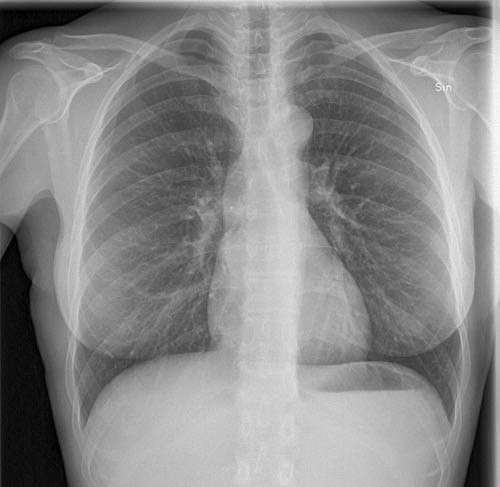

Först diskuterades det om jag skulle bli inlagd för säkerhetsskull. Men Sigrid frågade om jag kan klara mig själv och det tycker jag ändå. Sedan ringde hon Per Ljungman och efter att ha kontrollerat min saturation (förmågan att syresätta mig) så lät hon mig åka hem med uppmaning att ringa så fort jag blir sämre. Dessutom sa sköterskan Kerstin att hon kommer ringa i morgon bitti för att kolla status. Jag är som vanligt under fin uppsikt. Vi får se vad blododlingarna visar under nästa vecka, men förhoppningsvis kommer jag vara mycket piggare då.